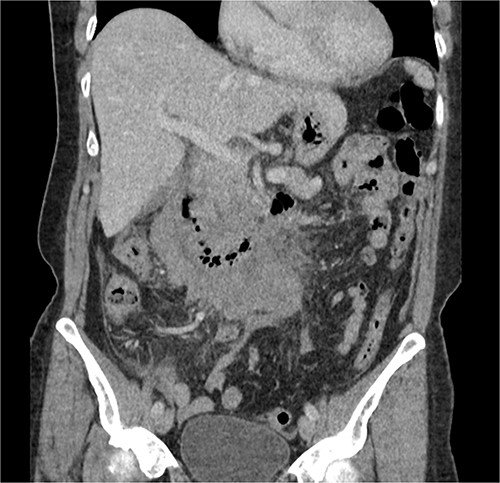

The radiologist suggested a computer tomography (CT) scan to further explore the potential causes for this fluid. The CT abdomen and pelvis revealed extensive oedema and induration surrounding the duodenum with a complex hyperdense fluid, extending from this site to the paracolic gutters and into the pelvis. While these findings are suspicious of a paraduodenal hemorrhage from a ruptured duodenal ulcer and hemoperitoneum, they were not typical for perforated duodenal ulcer or erosion into the blood vessels. Differentials were an infiltrating mass either fibrotic or of a lymphoproliferative origin. However, this could not explain the complex fluid in the abdomen (Figs 1 and 2).

CT abdomen, axial view. Hyperdense fluid centered around the duodenum and tracking into the paracolic gutters. Appearance concerning for paraduodenal hemorrhage, infiltrating mass was considered less likely.